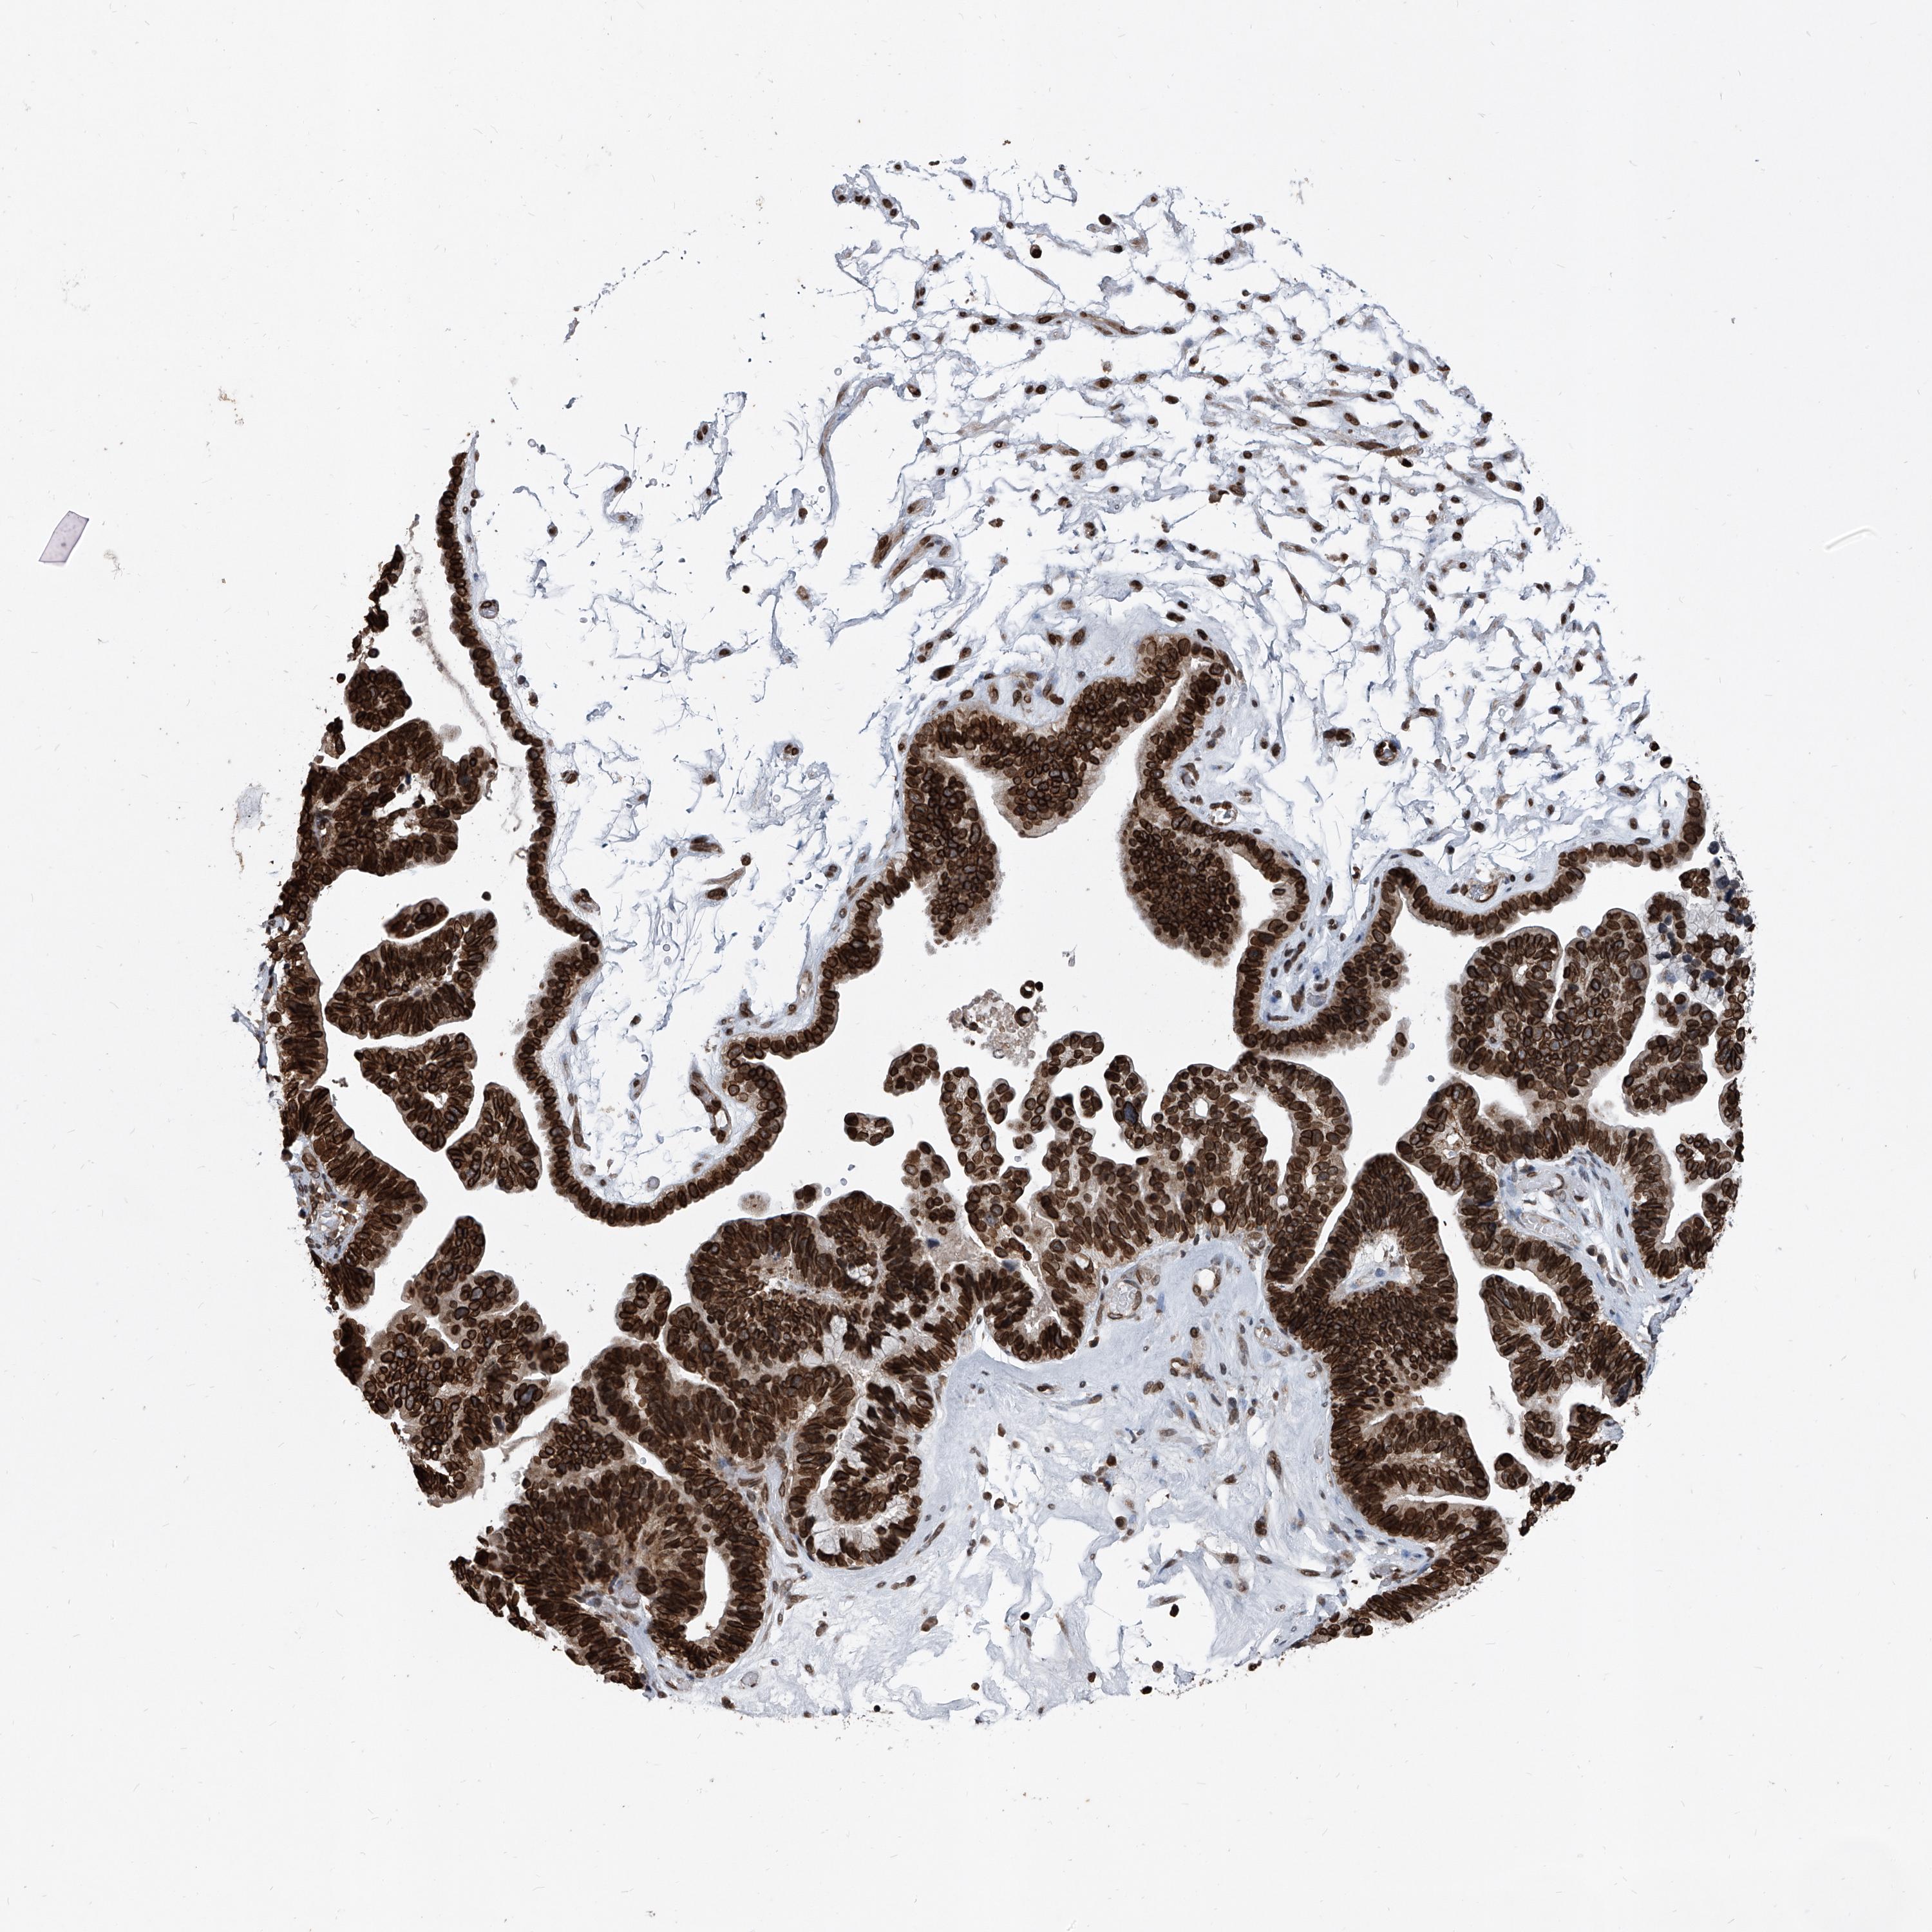

PHF20